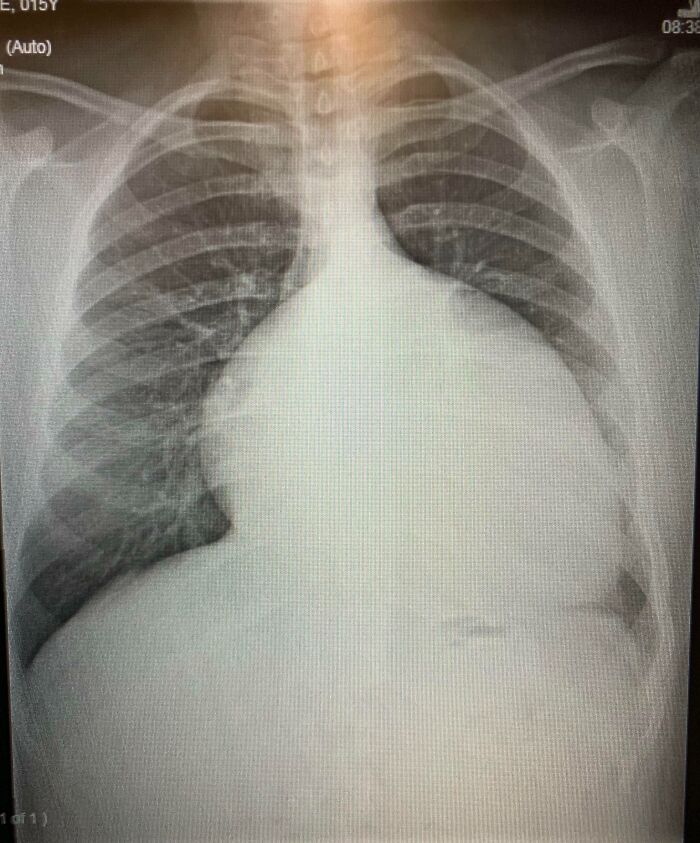

#5 Moje zväčšené srdce vo veku 15 rokov (2012) pred operáciami